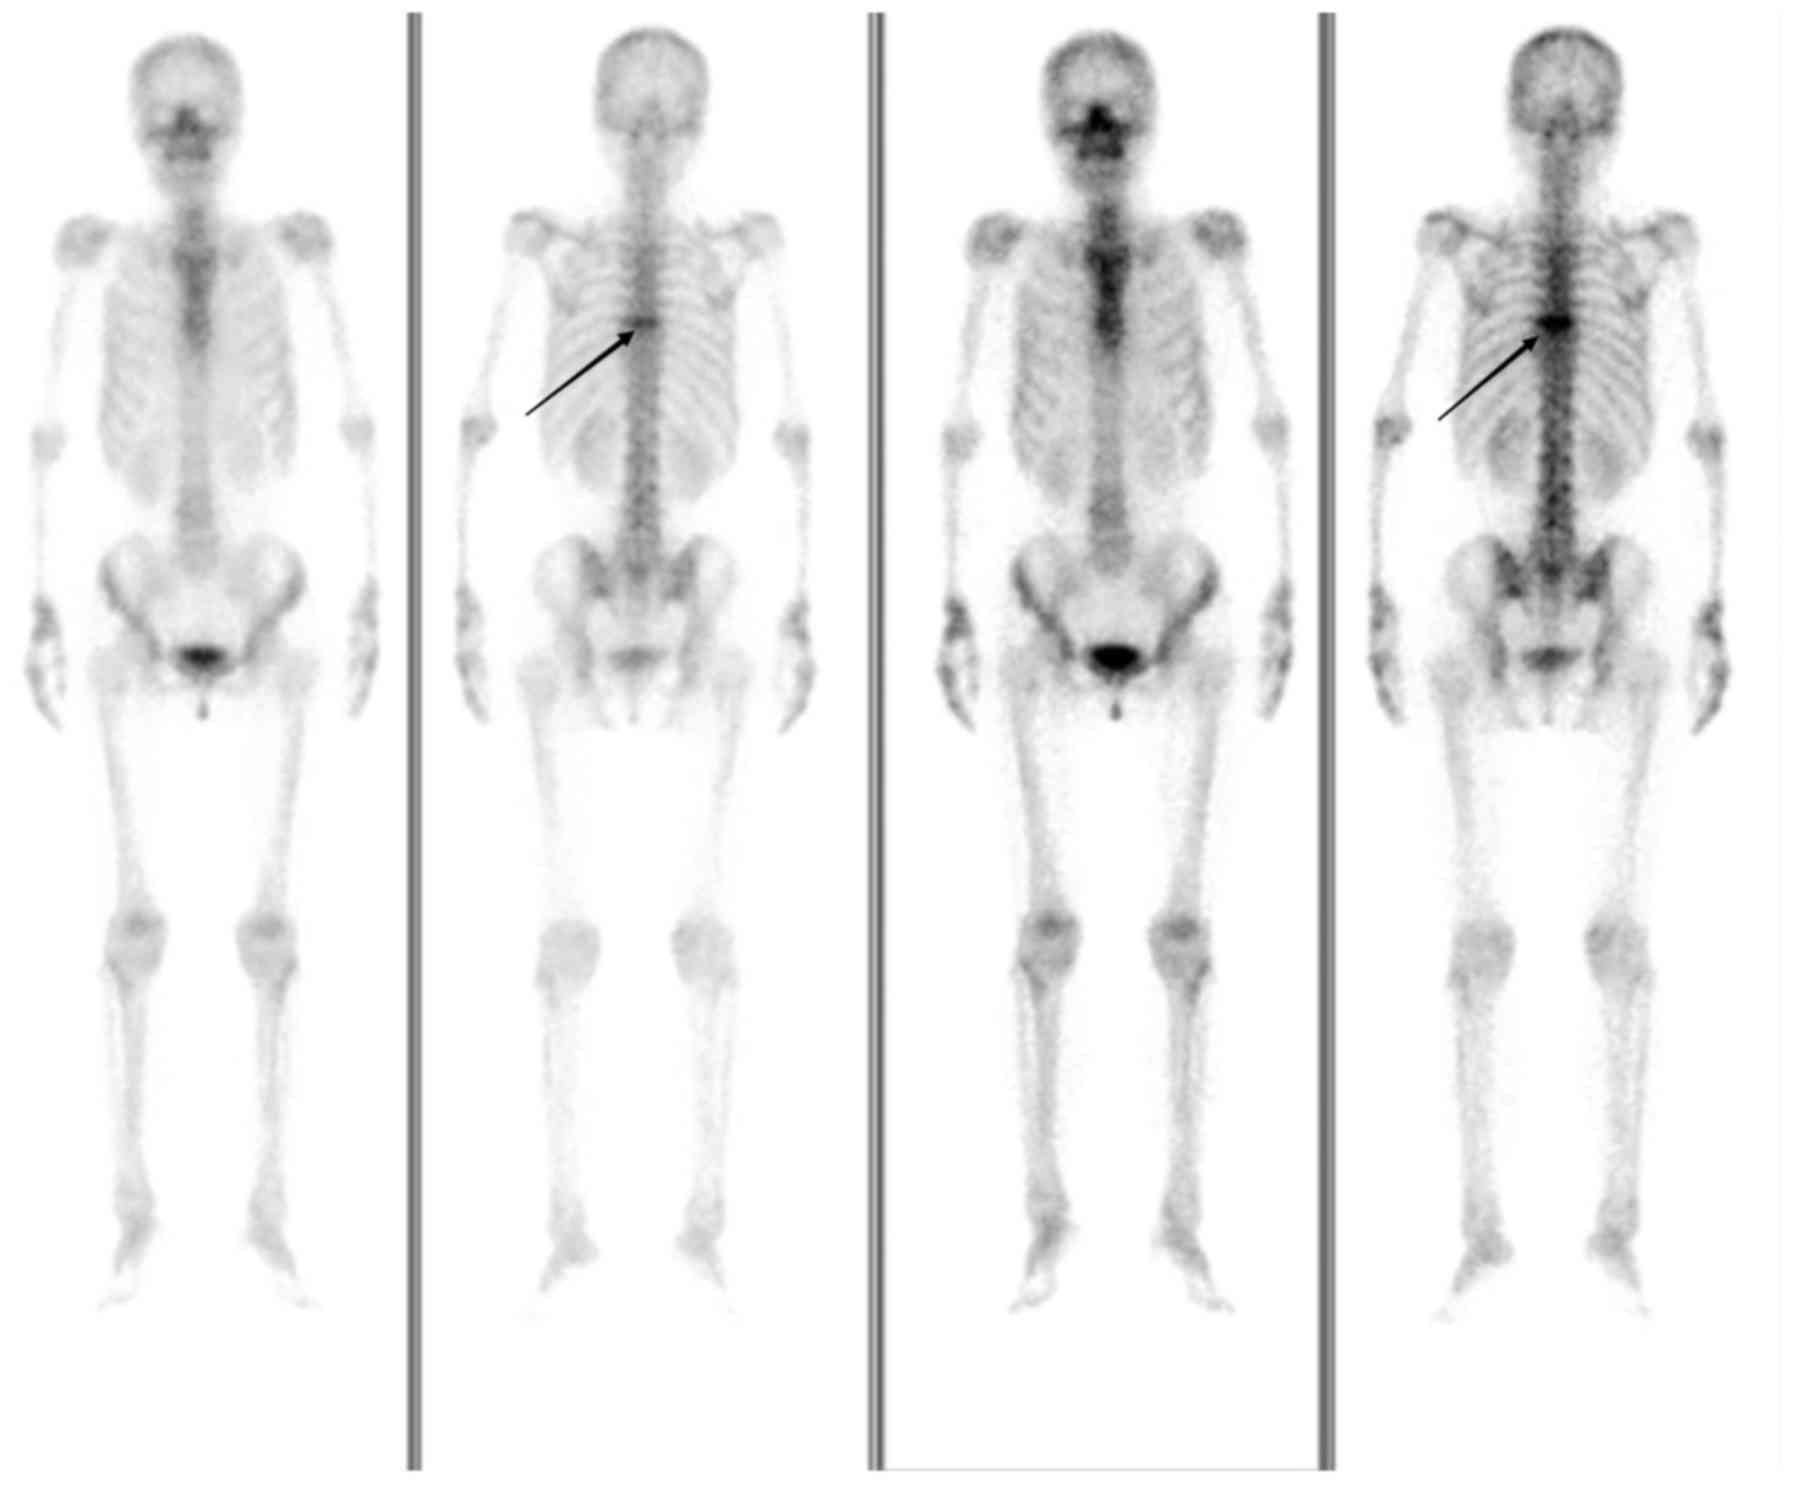

Following 2 cycles of chemotherapy, CT scans of the pelvis, abdomen and thorax were negative. Following the 6 cycles of chemotherapy, a CT scan (Fig. 6) and whole-body bone imaging (Fig. 7) revealed evidence of thoracic vertebral body metastasis. However, the abdomen and pelvis were negative for NHL. The patient received palliative radiation (36 Gy in 20 fractions) for the vertebral body metastasis. At time of publication, the patient was reviewed every three months and no recurrence or other metastasis had been observed.